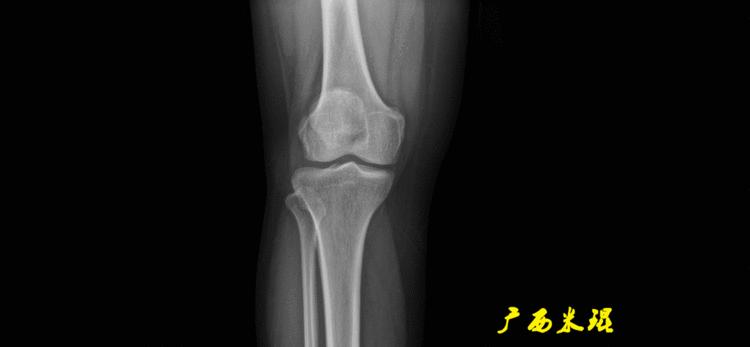

(2)膝关节中心

膝关节中心点常用的有5个不同的定位方法,分别是股骨髁中点、股骨髁间窝顶点、膝关节间隙水平软策划中点、胫骨髁间嵴中点和胫骨平台中点,我们可以根据具体情况来选用。